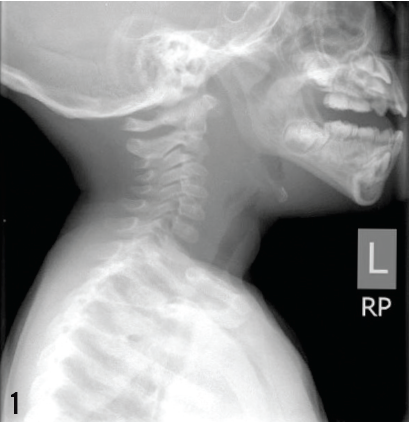

Roger Rossi, DO; Kathryn Eckert; Dawn Deike, DO; Chun Ho, MD

This article presents a case of severe DCM in a 15-year-old boy with DMD who presented clinically with gastrointestinal symptoms.